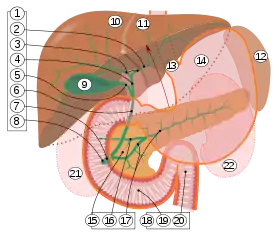

9. Gallbladder.

10–11. Right and left lobes of liver.

12. Spleen.

13. Esophagus.

14. Stomach.

15. Pancreas: 16. Accessory pancreatic duct, 17. Pancreatic duct.

18. Small intestine: 19. Duodenum, 20. Jejunum

21–22. Right and left kidneys.

The front border of the liver has been lifted up (brown arrow).[2]